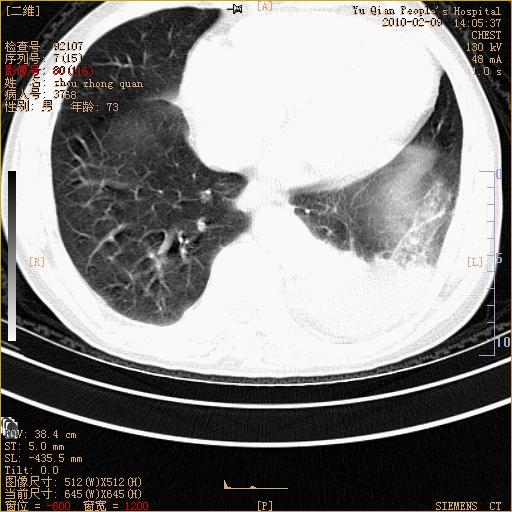

男性,73岁,咳嗽咳血数天,诊为肺ca伴左肺下叶后段阻塞性炎症、肺不张妥否?

右下肺有转移?

段性肺不张 还是查个支气管镜

段性肺不张,周围有阻塞性炎症、胸水, 还是查个支气管镜。

左下肺中央型肺癌伴结段形肺不张,左侧胸腔积液,纵隔内见部分增大淋巴结(反应性增生或转移)

左下基底干支气管明显变窄。

左肺下叶基底段支气管狭窄,左肺门增大,左肺下叶团片状病灶。中心型肺癌伴柱塞性炎症可能大,建议支气管镜检查。

左下肺中央型肺癌伴节段性肺不张,左侧胸腔积液,纵隔内见肿大淋巴结

左下基底段支气管变窄。建议进一步纤支镜检查。

1、左肺下叶后基地段肺癌伴阻塞性炎症,左下肺门淋巴结转移。2、左侧胸腔积液。